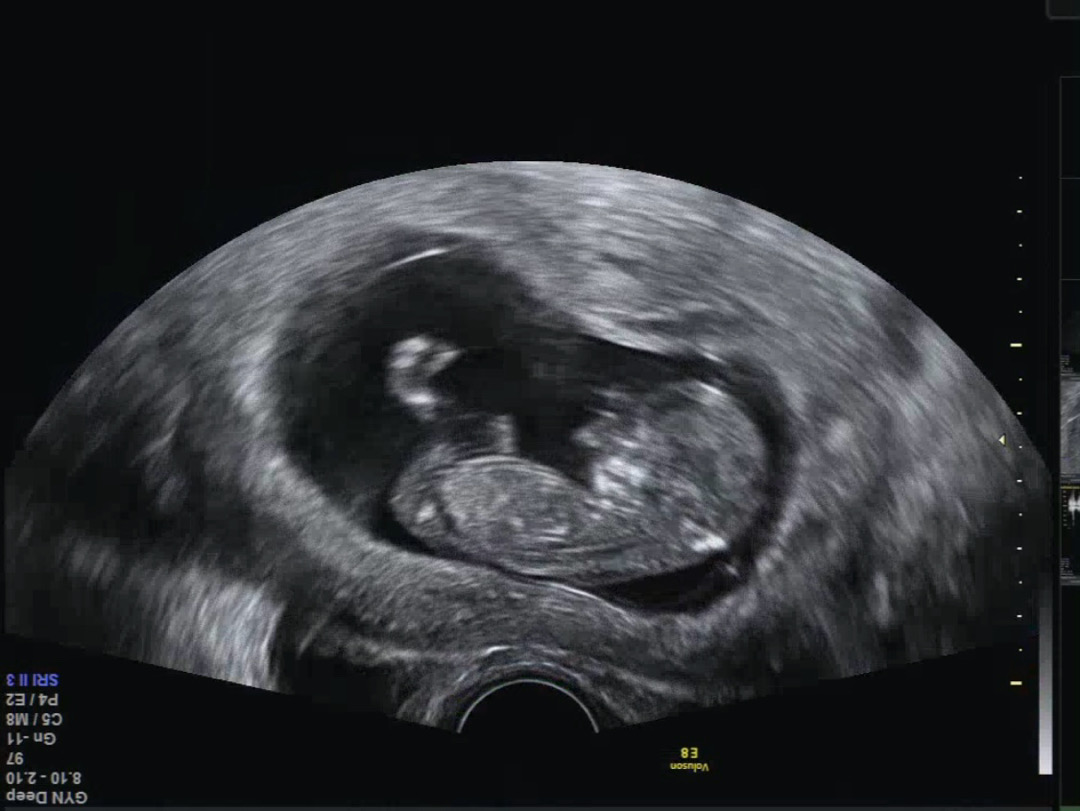

한번 봐주세용 11주 4일❤️

아들일까요 딸일까요 아들 딸 둘 다 좋고, 아직 빠른것도 알지만, 너무 궁금한걸요😭

각도법 볼 수 없는 사진이네요 ㅠ 옆모습도 생식기 부위가 보여야해요

으앙 이번주에 가는데 다시 잘 찍어와볼께요😭